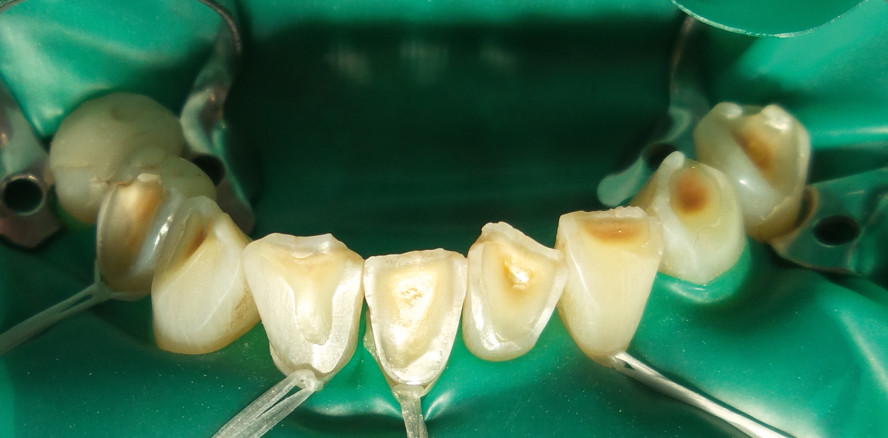

Bisserhöhung planen: Man legt dem Patienten die Ecke eines Zellstofftupfers auf die mittleren Schneidezähne und lässt ihn normal zubeißen. Nun kann man die prospektive Biss­erhöhung erkennen. Sie soll ein bis zwei Millimeter betragen. Bei fehlendem Frontkontakt muss man den Zellstofftupfer falten, bis eine solche Bisserhöhung entsteht. Okklusion vorbereiten: Der Schmelz wird leichthändig und trocken mit einem Polierdiamanten so angefrischt, dass alle kleinen Defekte (Abb. 1) hervortreten, um sie dann abzurunden bzw. zu exkavieren. Füllungen aus Komposit, Amalgam oder Keramik werden mit einem eckigen Diamanten aufgeraut (Abb. 2 und 14). Kleine okklusale Füllungen werden entfernt.

Fall 1: nur Oberkiefer (nur Seitenzähne)

Der Patient (55 Jahre) hatte Angst vor Kiefergelenkproblemen, die gemäß seinem Zahnarzt wegen der Bisssenkung entstehen könnten (Abb. 19). Er spürte allerdings keinerlei Beschwerden und störte sich nur etwas an den aufgespreizten Frontzähnen. Hiermit bestand eine ideale Indikation zur Erhöhung der Seitenzähne und Nichtbehandlung der Front, sodass sie durch den bloßen Lippendruck retrudieren kann. Zuerst wurden 7654+ erhöht (Abb. 1–13), gleich anschließend +4567 (Abb. 14–18). Arbeitszeit total knapp 2,5 Stunden, Preis 900 CHF (Abb. 20).